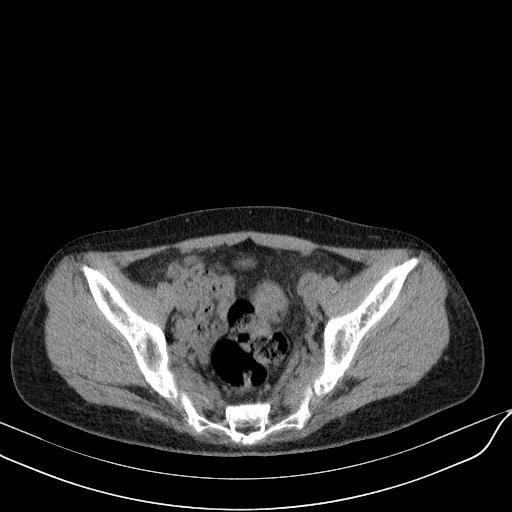

标题: CT23965:无外伤史,下腹痛 [打印本页]

标题: CT23965:无外伤史,下腹痛

肠道未准备,继续往下扫,乙状结肠占位不排除。建议钡灌或结肠镜检查。

乙状结肠占位不排除

回肠间质瘤?

肠道肿瘤,建议行钡剂灌肠检查。